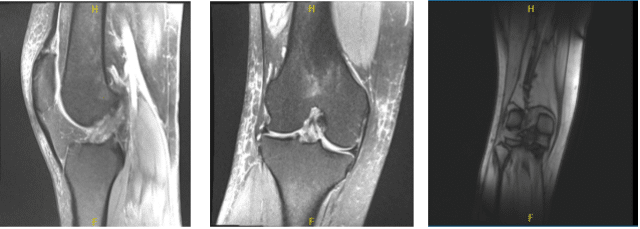

MRI-3T Right Knee non-contrast

Examination of the lateral tibiofemoral compartment showed fraying and tearing of the lateral meniscus and the posterior horn as well as vertical tear of the body of the lateral meniscus. Debridement of lateral meniscus was performed.

There was a free edge tear of the anterior horn of the lateral meniscus also, which was debrided. Decision was made to repair the lateral meniscus considering that it was reducing very well.